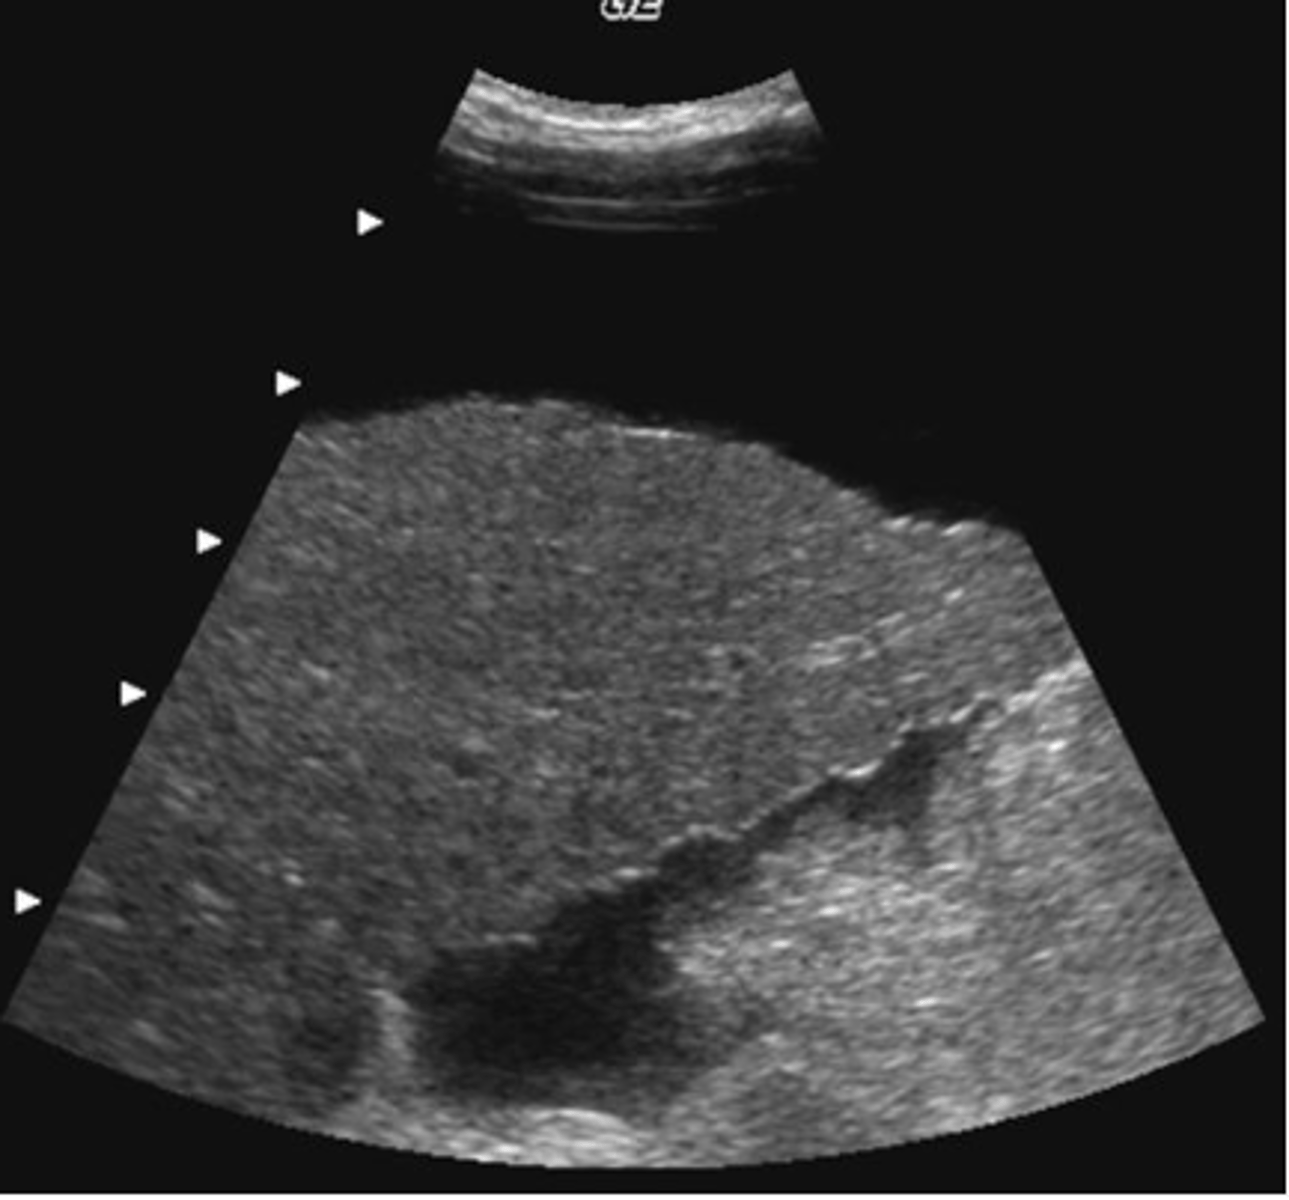

a. cirrhosis

In the image below, the surface nodularity of the liver is indicative of:

b. metastatic disease

c. hepatitis

d. fatty infiltration

e. hydatid disease